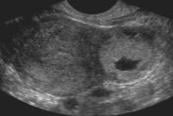

- Gestational Sac > 25 mm without a fetal pole (Illustration 14)

- Illustration 14. Large empty gestational sac